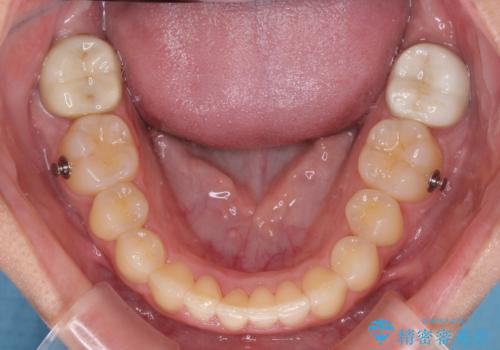

- 上顎の重なっている前歯を気にして来院された患者様です。

八重歯改善には抜歯が必要で、八重歯の移動量が多く、更には右側にずれている正中を改善する必要がありました。

インビザライン単体での治療は困難と判断し、補助装置により八重歯移動後にインビザラインを用いることとしました。

インビザラインでは治療期間が延びることが予想されたため、ワイヤー矯正を提案しましたが、セラミッククラウンが多く、壊すあるいは傷が付く可能性があることから、長期間であってもインビザラインを選択されました。